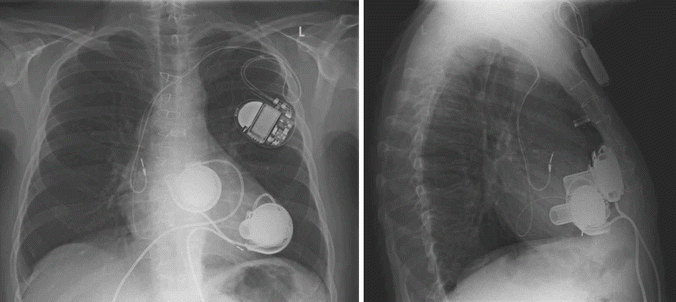

Fig. 31.2

Chest roentgenogram of a patient after implantation of two HeartWare HVAD® ventricular assist devices for biventricular support. The right pump is connected to the anterior free wall of the right ventricle